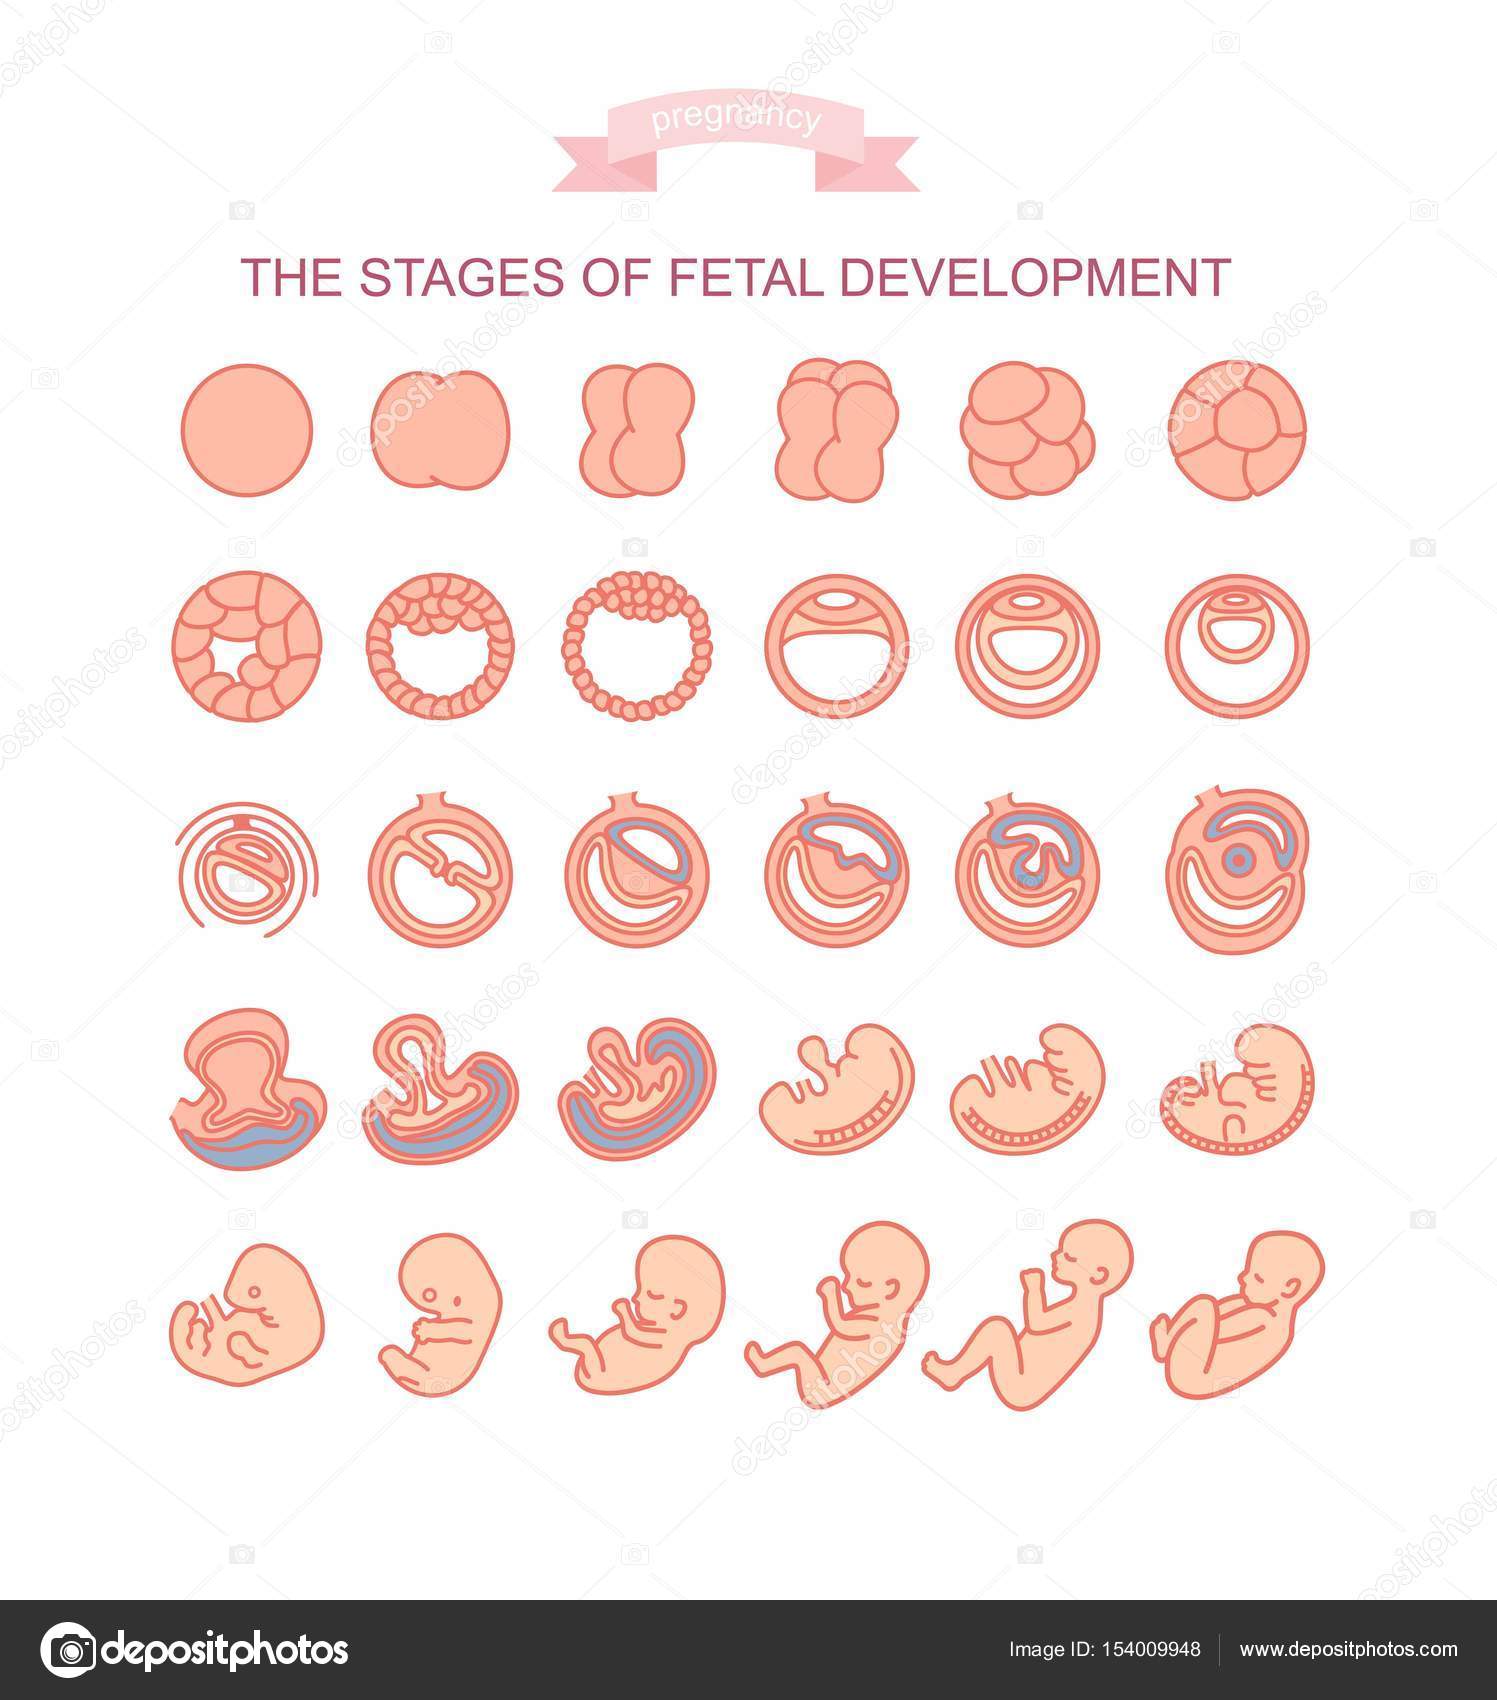

月成長過程で胚を胎児。人間の妊娠胎児または子の胎児妊娠の出生前のプロセス。ベクトル フラット インフォグラフィックのアイコンを設定のイラスト素材・ベクター Image 86554938。

胚発生妊娠ベクターのヒト胎児成長段階 - 妊娠のベクターアート素材や画像を多数ご用意 - 妊娠, ステージ, ヒトの胎児 - iStock。

Stockvektorbilden 胎児の成長のイラストAdobe Stock。

妊娠胎児の成長段階の開発。ベクトルのイラスト素材・ベクター Image 69587105。

胚の発達。妊娠ベクター図のヒト胎児成長段階。出生前のライフベビーステージのイラスト素材・ベクター Image 93225103。